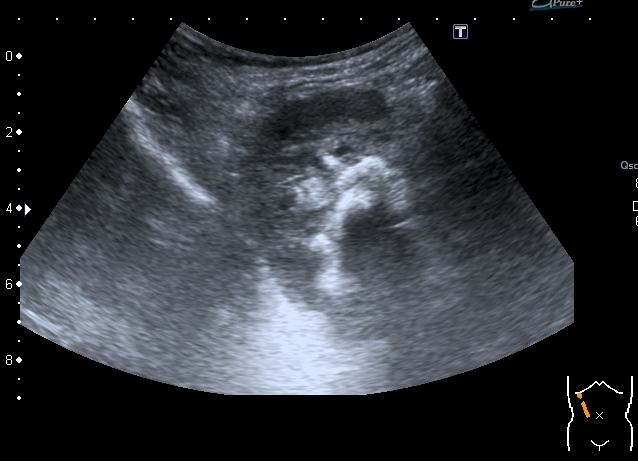

Ребёнок 4-х лет с терминальной гидроцефалией (объём мозгового черепа около 6 - ти литров на глаз), тетрапарезом, вторичным сколиозом 4-й степени, двухсторонним вывихом тазобедренных суставов, глуьокой умственной отсталостью поступил в детское хирургическое отделение. Мать отмечает в течение последних 2-х месяцев кровянистые выделения на памперсе, в последние несолько недель беспокойство ребёнка. В анализе мочи - гематурия.

Произведено УЗИ с бльшими техническими трудностями из - за сопутствующей ортопедической и неврологической патологии

Сокращённый мочевой пузырь

Он же в поперечном скане

Мочеточники в нижней трети

Правая почка

Левая почка

Нейрогенный мочевой пузырь (?), МКБ, конкремент мочевого пузыря, двухсторонний мегауретер, конкремент правой почки.